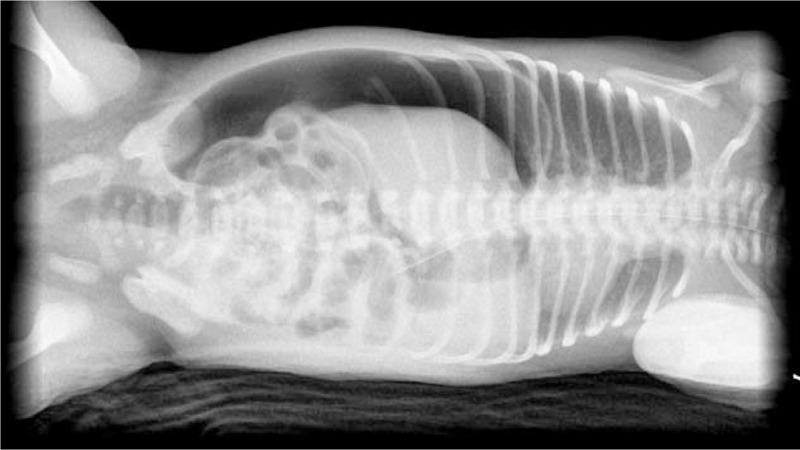

Two neonates received a diagnosis of gastric perforation based on clinical presentation and imaging studies. The 2 patients underwent emergent surgery, which yielded favorable outcomes.

两名新生儿根据临床表现和影像学检查被诊断为胃穿孔。这两名患者接受了急诊手术,结果良好。